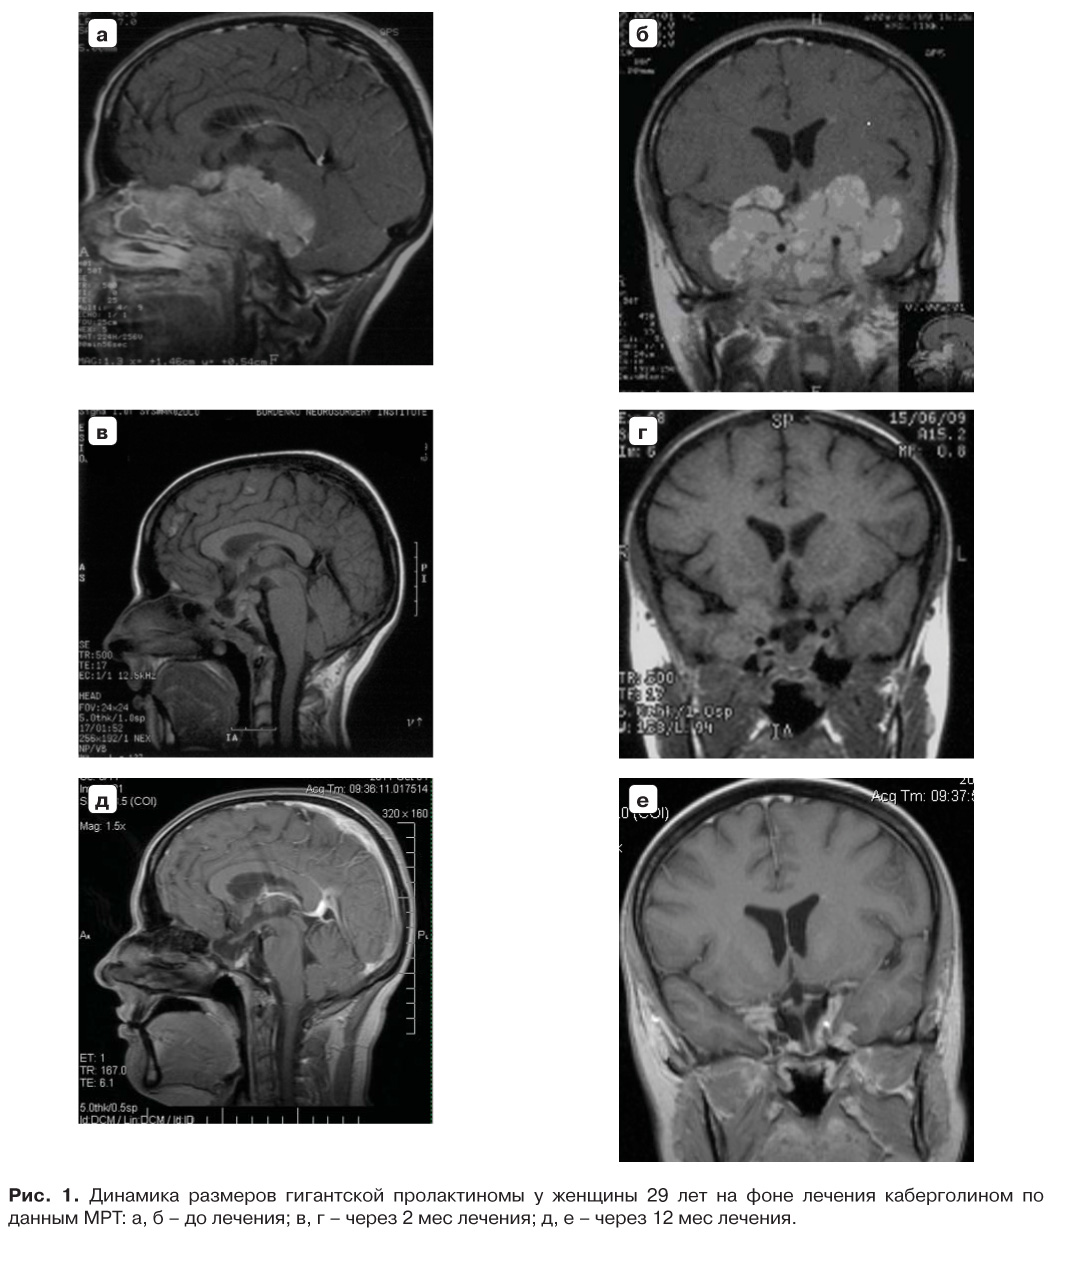

При обследовании: рост – 170 см, вес – 44 кг, индекс массы тела – 15 кг/м2 (норма 18–25). Артериальное давление – 105/70 мм рт. ст., частота сердечных сокращений – 63 в минуту. При проведении МРТ головного мозга обнаружена гигантская многоузловая опухоль гипофиза эндо-супра-инфра-ретро-анте-латероселлярной локализации, заполняющая клиновидную пазуху, распространяющаяся в оба кавернозных синуса, в правые отделы решетчатой кости, в парастволовые цистерны с компрессией ствола мозга; максимальный диаметр аденомы составил 8,7 см (рис. 1 а, б). При нейроофтальмологическом осмотре диагностированы зрительные нарушения в виде битемпоральной гемианопсии и снижения остроты зрения (VIS OD = 0,6), правостороннего экзофтальма (3 мм). В гормональном анализе крови уровень пролактина (ПРЛ) – 2218283 (40–530) мЕд/л, макропролактин – 34%, ТТГ – 1,29 (0,4–4) мЕд/л, св.Т4 – 13,0 (10–22) нмоль/л, кортизол – 701 (138–690) нмоль/л, ЛГ – 0,993 (1,9–12,5) мЕд/л, ФСГ – 7,18 (2,5–10,2) мЕд/л, эстрадиол – 76 (72–529) пмоль/л, тестостерон – 0,894 (0,5–2,6) нмоль/л. Выявлено значимое повышение уровня ПРЛ, данных за гипотиреоз и гипокортицизм не получено. В психоневрологическом статусе нарушений не выявлено.

При контрольном МРТ-исследовании, выполненном через 2 мес от начала лечения, отмечено существенное уменьшение размеров опухоли (рис. 1 в, г). Динамика уровня ПРЛ представлена на рис. 2. Нормализация ПРЛ отмечена через 6 мес лечения, однако у пациентки сохранялась аменорея. По данным УЗИ органов малого таза толщина эндометрия не превышала 2 мм, в связи с чем с ноября 2010 г. назначена заместительная гормональная терапия (ЗГТ) (фемостон 1/10), на этом фоне отмечались регулярные менструальные выделения. На фоне пробной отмены препарата фемостон на 2 мес через 6 и 18 мес от начала его приема менструальный цикл не восстанавливался, и терапия была продолжена в постоянном режиме.

Рис. 1. Динамика размеров гигантской пролактиномы у женщины 29 лет на фоне лечения каберголином по данным МРТ: а, б – до лечения; в, г – через 2 мес лечения; д, е – через 12 мес лечения.

При МРТ через 12 мес отмечен полный регресс опухоли, формирование “пустого” турецкого седла. При последующих МРТ-исследованиях, проводимых ежегодно в интервале с 2009 по 2017 г., признаков продолженного роста опухоли не выявлено.